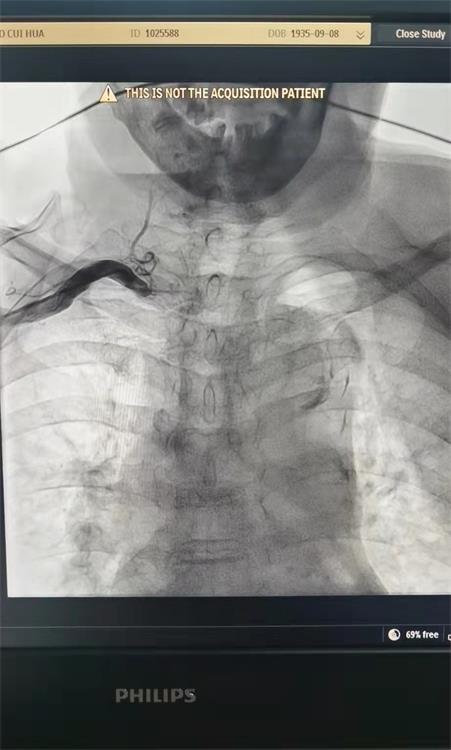

进一步诊断后发现,患者血管迂曲、钙化严重,造影管无法通过,家人几乎决定放弃,但我院胸痛中心医护人员为了挽救病人生命,再次结合CT,反复调整导丝,经过多番尝试,导丝终于到位。

造影提示前降支主要血管闭塞,需紧急开通血管。就在手术过程中,患者突发心跳慢、血压低,导管室医护人员立即进行抢救,经过大家共同努力,患者转危为安,最终完成前降支支架植入。